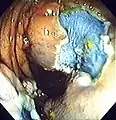

![]() Colonoscopy being performed | |

Colonoscopy (/ˌkɒləˈnɒskəpi/) or coloscopy (/kəˈlɒskəpi/)[1] is a medical procedure involving the endoscopic examination of the large bowel (colon) and the distal portion of the small bowel. This examination is performed using either a CCD camera or a fiber optic camera, which is mounted on a flexible tube and passed through the anus.[2][3]

The purpose of a colonoscopy is to provide a visual diagnosis via inspection of the internal lining of the colon wall, which may include identifying issues such as ulceration or precancerous polyps, and to enable the opportunity for biopsy or the removal of suspected colorectal cancer lesions.[4][5]